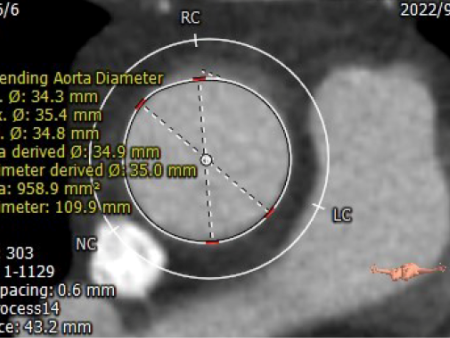

CT测量

瓣环周长:67.2mm

LVOT周长:67.5mm

瓣环上4mm:66.3mm

瓣环上6mm:65.4mm

左冠开口高度:13.2mm

右冠开口高度:11.7mm

瓣环角度:59°

升主动脉周长:109.9mm